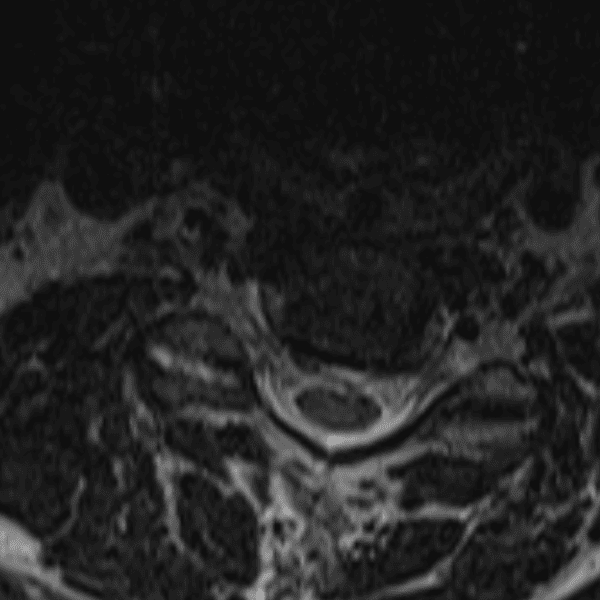

Simulates call by including subtle or difficult cases and some normals.

35 cases